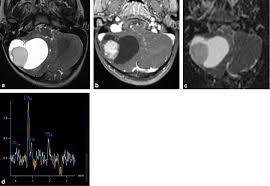

Pdf Le Gliome Du Tronc Cerebral Cause Rare De Vertige Central De L Adulte

visitez l'article complet ici : https://www.researchgate.net/publication/309710288_Le_gliome_du_tronc_cerebral_cause_rare_de_vertige_central_de_l'adulte